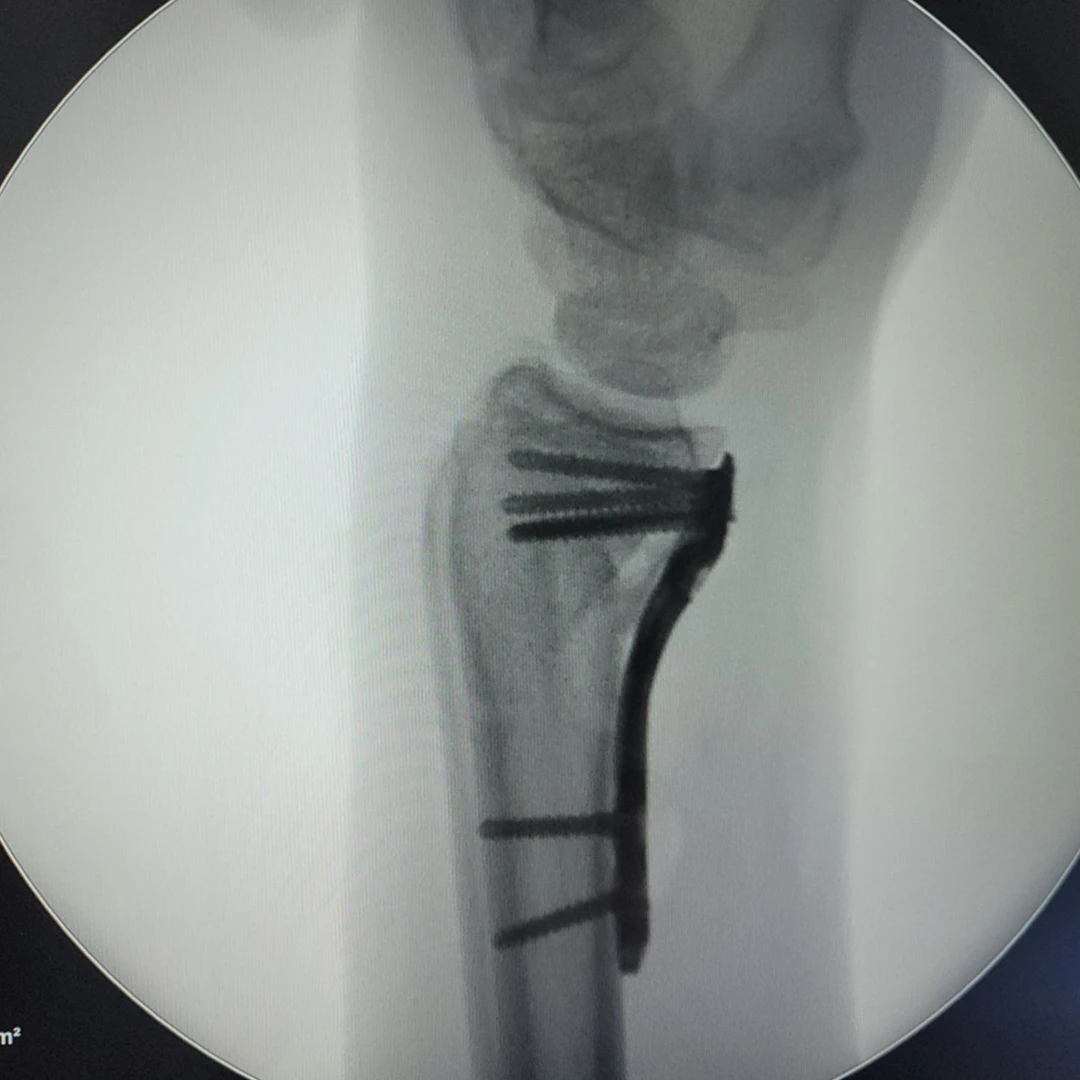

Placas para radio distal

RÁDIX Yuxta

Rádix Plus

Indicaciones

Fracturas en la porción distal del radio simples y complejas

con compromiso intra y extra articular.